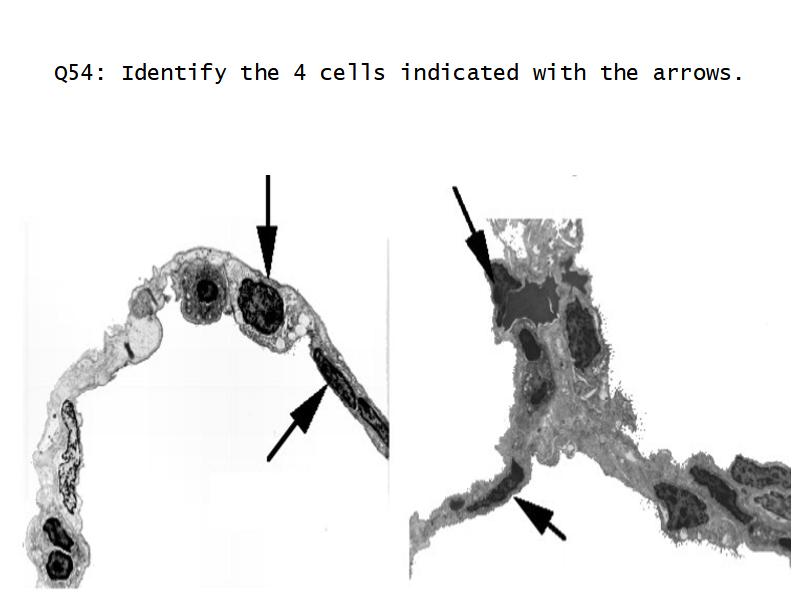

What cells are present?

Components of the Blood-Air Barrier?

Barriers

- Blood-air